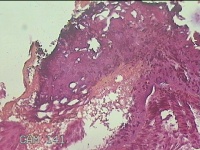

外阴赘生物

性别

女

年龄

33岁

临床诊断

外阴尖锐湿疣

一般病史

发现外阴尖锐湿疣4个月。

标本名称

大体所见

灰白暗红色不规则碎组织0.3x0.2x0.1cm一堆。

图3

良性病变,考虑湿疣。